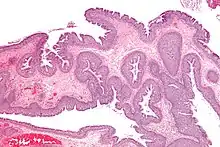

| Adénome tubulaire (villositaire, tubulovilleux) | Glandes tubulaires avec des noyaux allongés (au moins à faible teneur atypie) | Oui | ![]() |

||